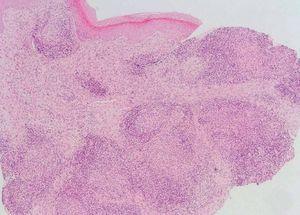

Se realizaron una biopsia cutánea (fig. 4) y cultivos microbiológicos.

Fig. 4.—Detalle histológico de las lesiones.

El estudio histopatológico mostró una epidermis normal. Bajo esta se observaron granulomas de células epitelioides y gigantes multinucleadas sin caseosis, rodeados por una corona linfocitaria, con tendencia a confluir y que ocupaban toda la dermis.

Las tinciones de Ziehl-Nielsen, BAAR, PAS y Giemsa fueron negativas.